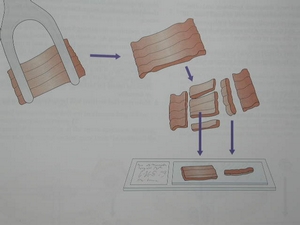

東方女性的大腿脂肪含量很高, 不輸西方人, 改善空間很大, 尤其近年來飲食西化之後. 上圖是身高165公分, 體重53公斤的某位消費者大腿抽出的脂肪圖, 每一瓶的單位是1800cc

東方女性的大腿脂肪含量很高, 不輸西方人, 改善空間很大, 尤其近年來飲食西化之後. 上圖是身高165公分, 體重53公斤的某位消費者大腿抽出的脂肪圖, 每一瓶的單位是1800cc